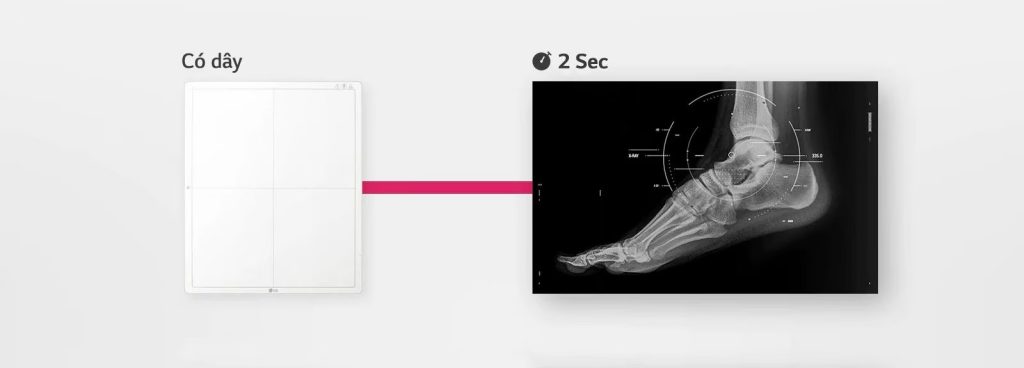

Hình ảnh sẵn sàng nhanh